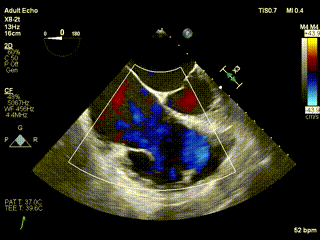

三例患者入院后,葛均波院士團(tuán)隊(duì)周達(dá)新教授、潘文志教授、張?jiān)床┦俊㈥惿┦考靶某业呐舜湔浣淌?、李偉教?/strong>對(duì)患者的情況進(jìn)行詳細(xì)評(píng)估和討論,最終決定為三例患者選擇LuX-Valve Plus40mm、50mm和50mm型號(hào)的瓣膜進(jìn)行手術(shù)治療。手術(shù)后即刻拔除氣管插管,術(shù)后患者三尖瓣反流癥狀得到顯著改善,復(fù)查心超結(jié)果顯示人工三尖瓣瓣膜支架固定穩(wěn)定,瓣葉關(guān)閉形態(tài)未見異常,未見明顯反流。